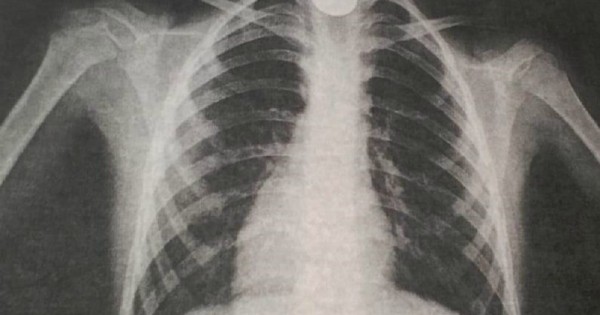

Белгілі болғандай, ойнап отырған 9 жастағы бала байқамай тиынды жұтып қойған. Бір сағаттан соң оның тыныс алуы қиындап, жағдайы нашарлаған. Бұдан соң, ол облыстық көпбейінді балалар ауруханасына жеткізілген. Өкпе жасушаларын түсірген рентгенография қорытындысы өңештің жоғарғы жағында бөгде заттың тұрғандығын анықтаған.

"Шұғыл түрде оны алу үшін Фолея (Испания) катетері (резеңке түтік) қолданылды. 2-3 см үрленетін 2 қуысты силиконды түтікті дене қуысындағы заттарды босату, дәрілік заттарды енгізу, шаю немесе оларды өткізу мақсатында сыртқы ортамен байланыстыратын резеңке түтікпен балаға жалпы наркоз салынды. Жалпы бұл әдіс оқыстан болған шұғыл жағдайда тиімді. Себебі уақыт өтіп кетсе, денеге бейімделіп кеткен затты алу қиынға соғады. Дәрігерлердің уақытылы көмек көрсеткенінің арқасында баланың жағдайы жақсарып, бала медициналық ем-шарадан кейін үйіне қайтарылды", - делінген хабарламада.